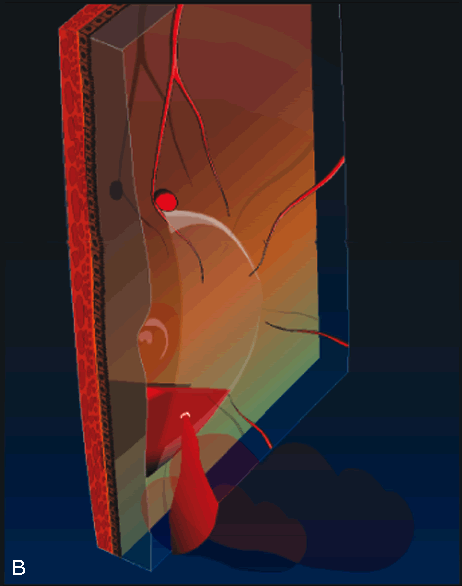

Pneumatic displacement of hemorrhage has been successfully employed in select cases of submacular hemorrhage from a macroaneurysm (Fig. 6). Subretinal blood results in irreversible damage to photoreceptors within 7 days.15–17 Many surgeons attempt to remove or at least displace this blood within 2 weeks and preferably within 7 days in an attempt to preserve central vision. A proposed alternative to vitrectomy with surgical evacuation of the blood is pneumatic displacement, in which a bubble of perfluorocarbon gas is injected into the vitreous cavity. The patient's head is then positioned such that the bubble's buoyant force squeezes the subretinal blood out of the macula and into the inferior fundus.18 Some surgeons precede the gas bubble with an intravitreal injection of tissue plasminogen activator (TPA) in order to lyse the blood clot; whether or not the TPA reaches the blood clot in sufficient quantities to cause an appreciable lysing effect is controversial.19 There is histological evidence that this technique in some cases causes shearing of the photoreceptor outer segments during the pneumatic displacement procedure.20

Fig. 6. Fresh submacular blood displaced from the macula with an intravitreal gas bubble injection. A. Air or gas is injected into the vitreous cavity. B. The patient is then placed in the face-down position such that the bubble slowly pushes the blood into the inferior fundus. The blood remains in the subretinal space but is displaced from the macula. Some surgeons precede the gas bubble with an intravitreal injection of tissue plasminogen activator in order to help lyse the blood clot.